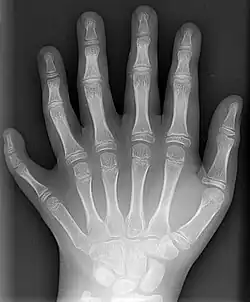

Radiografia de mão polidáctila.

Leves anomalias nos membros inferiores são relativamente comuns e costumam ser passíveis de correção cirúrgica. Podem ser isoladas ou sindrômicas, isto é, acompanhadas de outros defeitos. O período mais crítico para o desenvolvimento dos membros é a transição entre o primeiro e segundo mês de gestação (dias 24-36).[24]

• Polidactilia: presença de dígitos supranuméricos, ou seja, dedos extras, frequentemente formados de forma incompleta.[24]